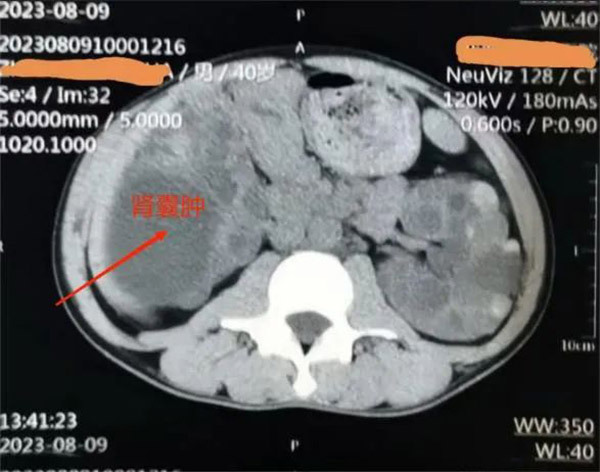

▲患者肾囊肿影像

38岁的王先生是一名多囊肾病合并巨大囊肿患者,因为工作原因需要经常出国。近半年来,他的囊肿逐渐增大并出现腰痛、腹胀的压迫症状,严重影响了王先生正常工作和生活。

肾内科主任洪敏接诊后,对王先生进行了详细的检查,结合其病情和身体情况,决定实施超声引导下经皮穿刺抽液囊肿硬化治疗。